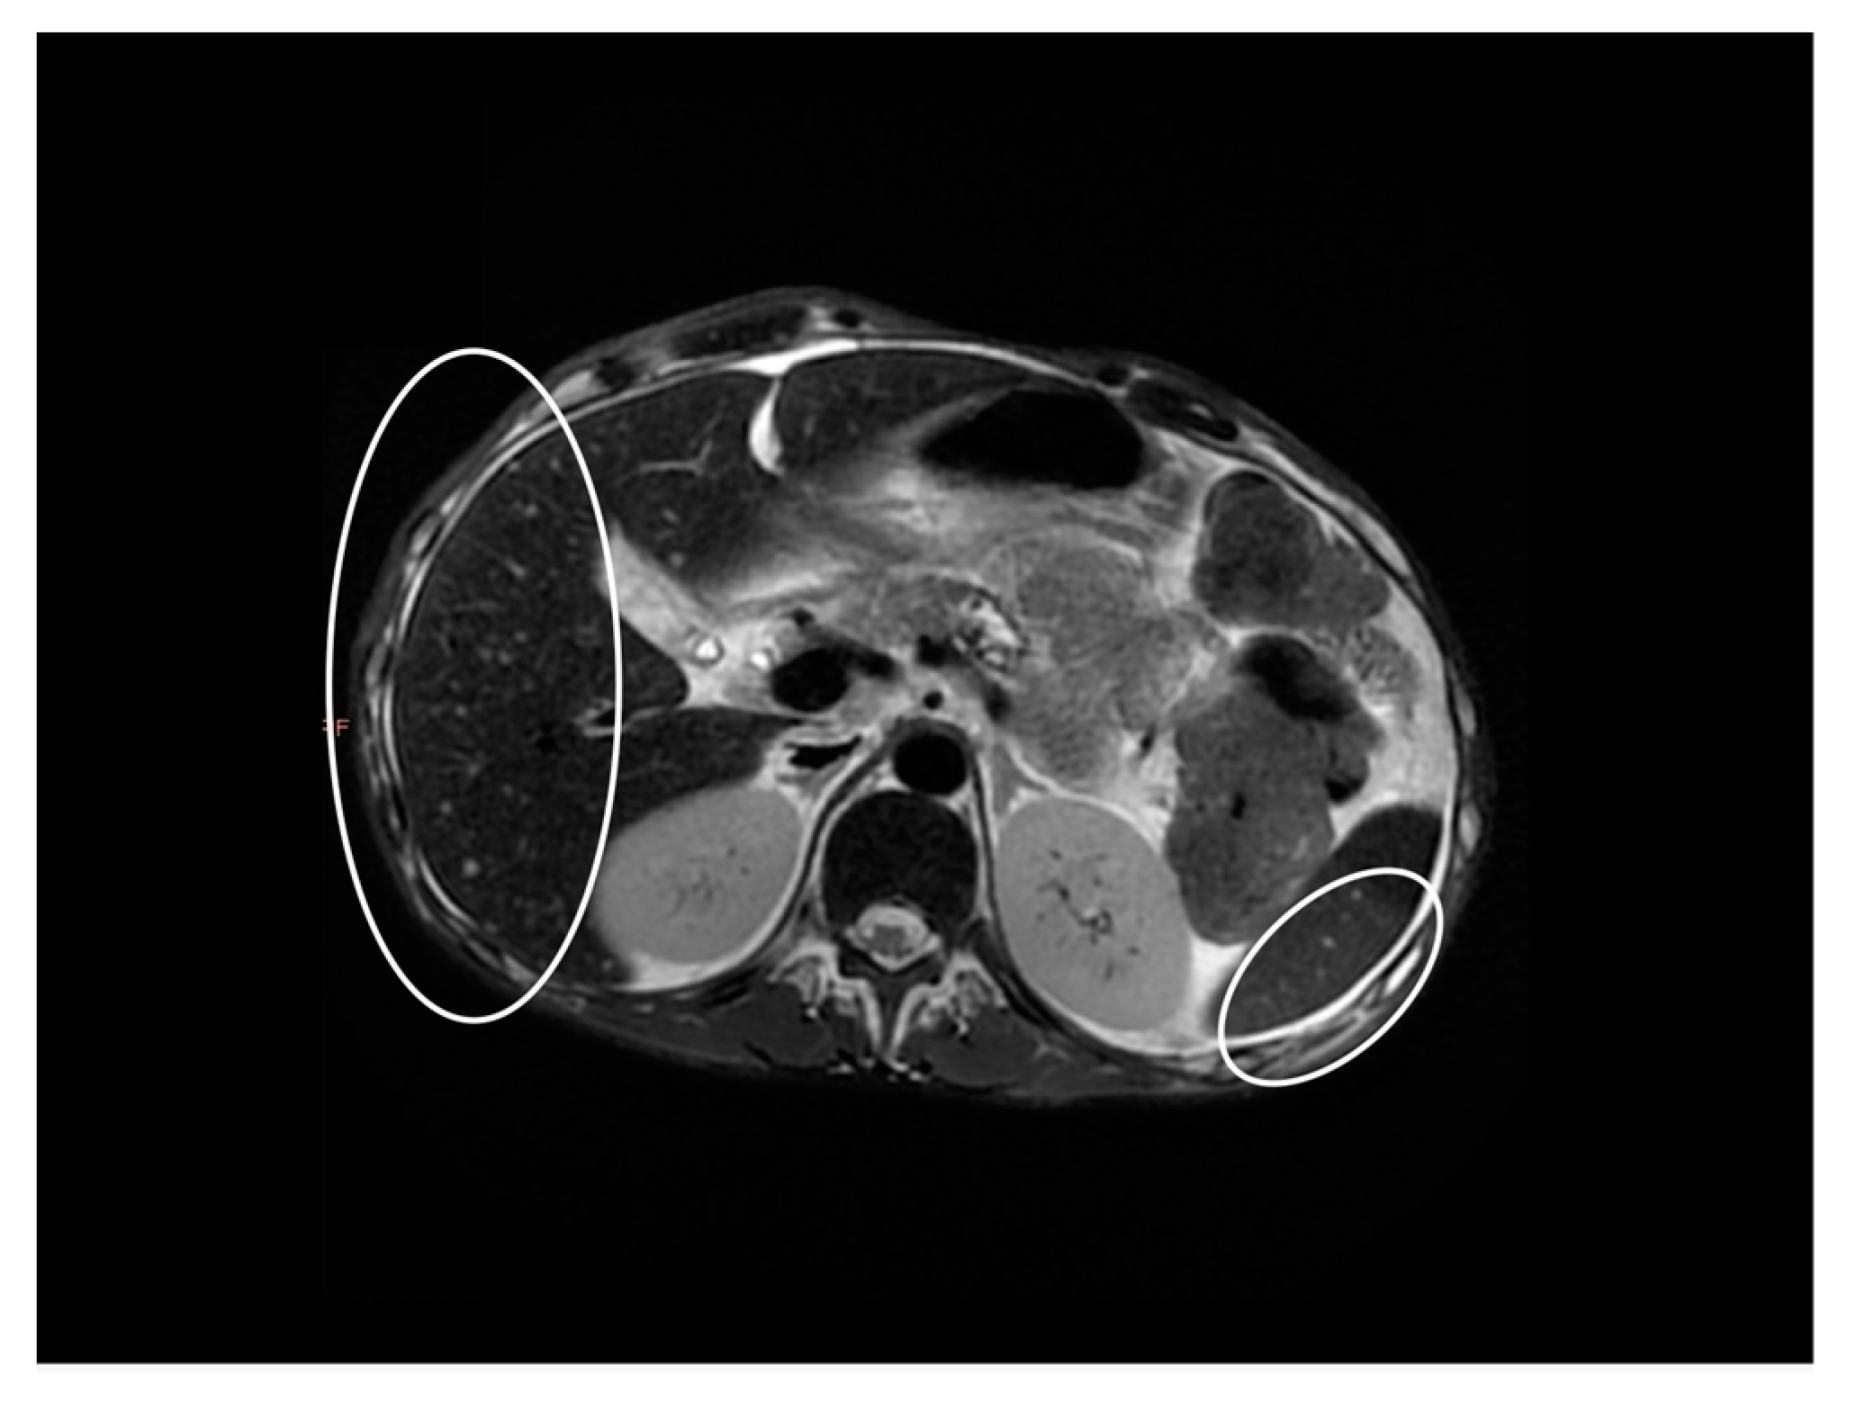

2. Case Report